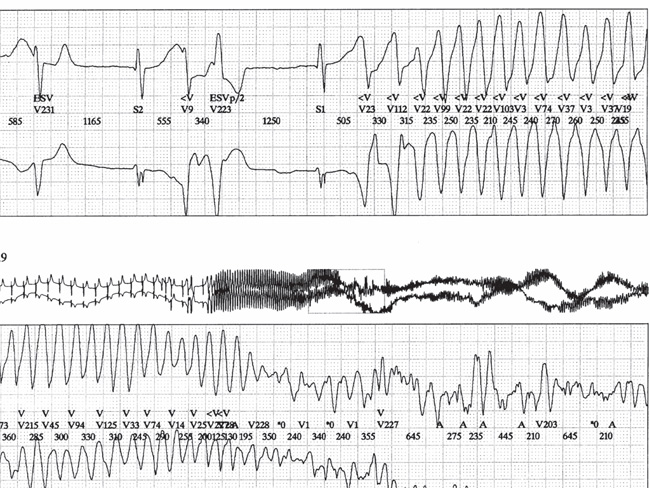

Advert Ventricular and point torsades volume 4, pages1177–1182(1990) Volume 4130 Accesses7 Citations Conclusions We have tried to give a general description of the traces of the ECG (obtained from, patients during cardiac resuscitation) that show progressive variations in the amplitude, and we have tried to develop a new set of diagnostic criteria. Two different arrhythmias were defined: Ventricular Fibrillation. This starts very soon after the previous ventricular complex, it appears as continuous oscillations that seem like a fine tremor (frequency in cycles per second range) and a amplitude that gradually varies to form lumps. We have no example of ventricular fibrillation that spontaneously reverts in normothermic conditions. Pointer screws. This is always initiated by a "specific electrical complex" and continues with progressive, regular and successive investments of the stroke (with a frequency in cycles per minute) and ends spontaneously after a ventricular pause. There are also two intermediate patterns: Double peaks. This arrhythmia, which occurs during long episodes of point torsades, has a slower frequency than the episodes of ventricular fibrillation that occur during hypothermia (an experimental condition that was used to allow the study of spontaneous termination of ventricular fibrillation). The anarchical interlude of long episodes of spontaneously reversible torsades. This is a preview of the subscription content, access options Buy single itemInstant access to the full PDF article. 34,95 €The calculation of the box will be completed during checkout. Subscribe to the journalImediate online access to all problems since 2019. The subscription will be renewed annually. 73,83 €The tax calculation will be completed during checkout. References Dessertenne F. Considerations sur l'ECG de la fibrillation ventriculaire. Arch Mal Coeur 1964;57:1421-1437. Dessertenne F. La fibrillation ventriculaire. Royal Cardiol Angeiol Int 1964;13:235–294. Dessertenne F. La fibrillation ventriculaire. Semin Hop Paris 1964;40:1791-1794. Dessertenne F. The tachycardie ventriculaire à deux foyers oposés variables. Arch Mal Coeur 1966;59:263–272. Dessertenne F. Le complexe electrique ventriculaire à phase lente prolongée. Semin Hop Paris 1967;43,8/2:539-541. Dessertenne F, Fabiato A, Coumel P. A capitre nouveau d'ECG. The progressive variations of l'amplitude de l'ECG. Royal Cardiol Angeiol Int 1966;15:241–258. Dessertenne F. Considerations sur l'activité auriculaire de l'arhythmie complete. Semin Hop Paris 1966;42,3/1:183–193. Dessertenne F, Fabiato A, Bouvrain Y. Considerations sur un accès de tachyarhythmie paroxystique. Arch Mal Coeur 1967; 60.6:884–892. Lutembacher R. Syndrome de Stokes-Adams par hyperactivité du centre ventriculaire dans le bloc du faisceau de His. Presse Medicale 1945;4:38. Dessertenne F, Coumel P, Fabiato A. Traitement des troubles du rhythme du coeur. Ency Medico-Chirurgicale 1968;6(25318A10). You can also search this author in You can also search this author in You can also search this author in Additional Information Translation of: La Presse Medicale, 77:193-196, 1969 This article is reprinted from the original by the permission of the journal and, where appropriate, from the authors. There are no reprints available. Rights and permits About this article Cite this article Dessertenne, F., Coumel, P. " Fabiato, A. Ventricular fibrillation and point torsades. Cardiovasc Drug Ther 4, 1177–1182 (1990). https://doi.org/10.1007/BF018565184, Question Date: August 1990DOI: Keywords Access Options Buy Unique ArticleInstant access to full article PDF. 34,95 €The calculation of the box will be completed during checkout. Subscribe to the journalImediate online access to all problems since 2019. The subscription will be renewed annually. 73,83 €The tax calculation will be completed during checkout. Announcement More than 10 million scientific documents available Not connected - 54.179.187.232 Not affiliated © 2021 Springer Nature Switzerland AG. Part of .

Short-Coupled Variant of "Torsades de Pointes" and Polymorphic Ventricular Tachycardia

Typical record with Torsade de Pointes ventricular tachycardia that... | Download Scientific Diagram

Cureus | Torsades de Pointes and Prolonged Self-Terminating Ventricular Fibrillation Induced by Amiodarone